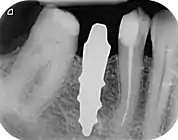

A new attempt was made by Pirker et al 2004 in a human trial with root analogue zirconia implants, but this time by applying differentiated osseoingration on the surface. In 2011 he reported 90% success rate with this method in a 2.5 year human trial.[11]

- Pirker, W; Wiedemann, D; Lidauer, A; Kocher, A (2011). "Immediate, single stage, truly anatomic zirconia implant in lower molar replacement: a case report with 2.5 years follow-up". International Journal of Oral and Maxillofacial Surgery. 40 (2): 212–6. doi:10.1016/j.ijom.2010.08.003. PMID 20833511.